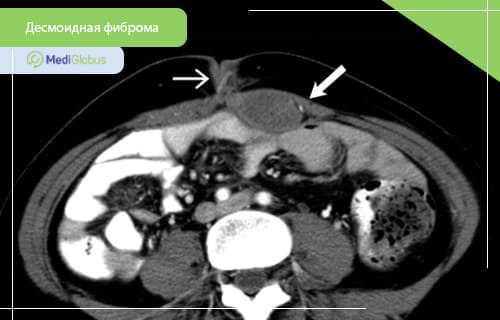

КТ часто используется во время диагностики десмоидных фибром. Метод особенно полезен при внутрибрюшных поражениях. Опухоли, возникающие в брюшной полости, чаще всего вовлекают брыжейку, хотя могут поражаться и другие участки. КТ может предоставить важную информацию, необходимую для планирования операции, такую как расположение соседствующих сосудов и органов. Такие осложнения, как кишечная непроходимость, ишемия кишечника и гидронефроз, также легко выявляются на КТ.